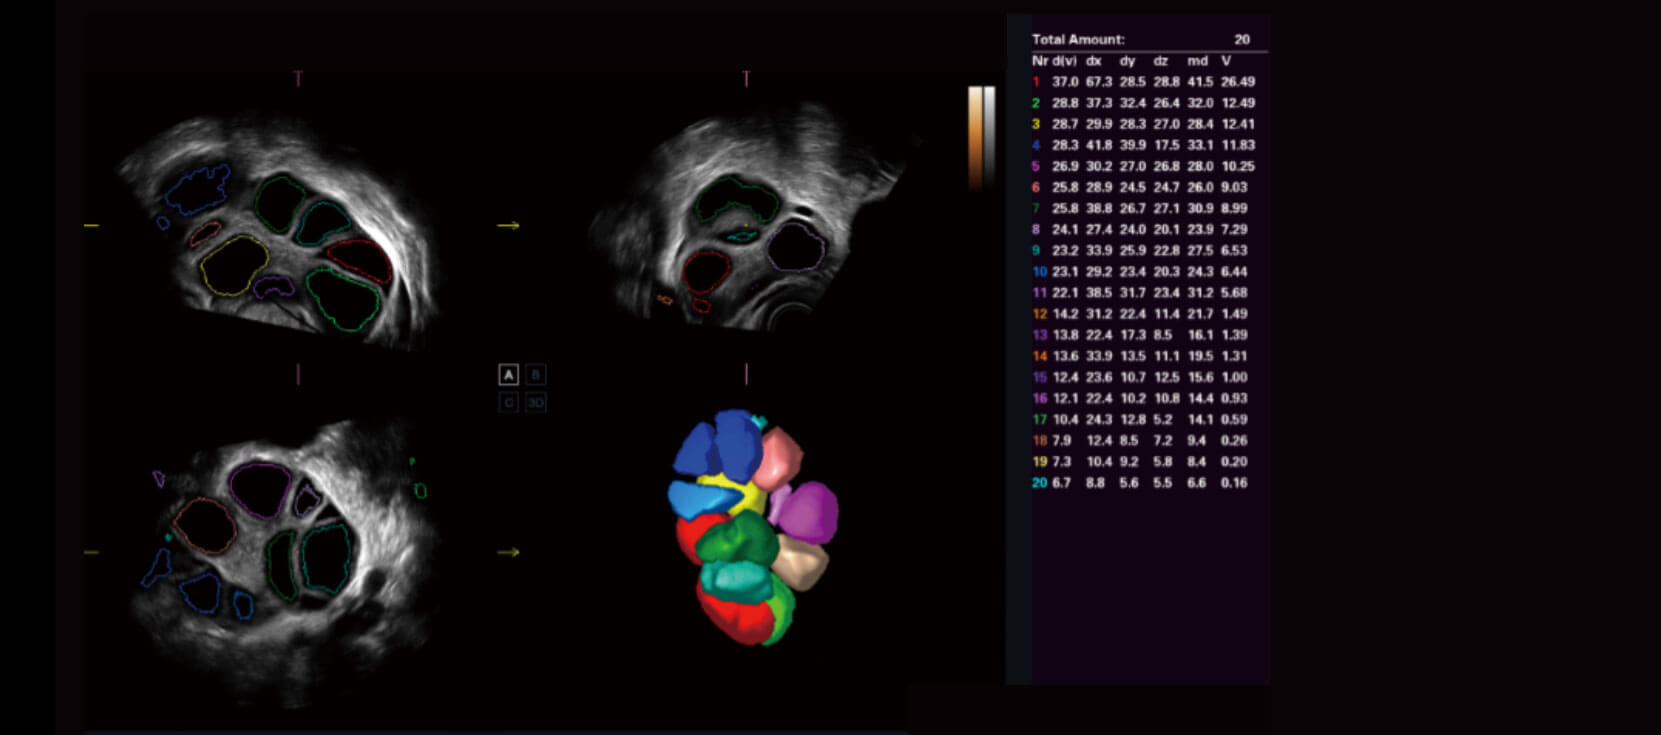

AVC-Follicle

Tính toán thể tích tự động cho nang trứng

Tự động xác định và đo nhiều nang trứng từ hình ảnh thể tích 3D

Các nang trứng được tự động sắp xếp theo kích thước với mã màu

Tăng tốc báo cáo đánh giá nang trứng với đồ họa màu được thiết kế